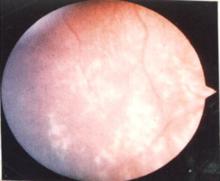

典型的LHON首發症狀是視物模糊,隨後的幾個月之內出現無痛性、完全或接近完全的失明

德國眼科醫生leber。通常是兩眼都受累,或者一隻眼睛失明不久,另一隻也很快失明。視神經和視網膜神經元的退化是LHON的主要病理特性。另外還有周圍神經退化、震顫、心臟傳導阻滯和肌張力的降低。LHON通常在20~30歲時發病,但發病年齡範圍可從兒童時期到70多歲。該病通常存在性別差異,男性患病風險一般是女性的4~5倍,但原因尚不清楚。